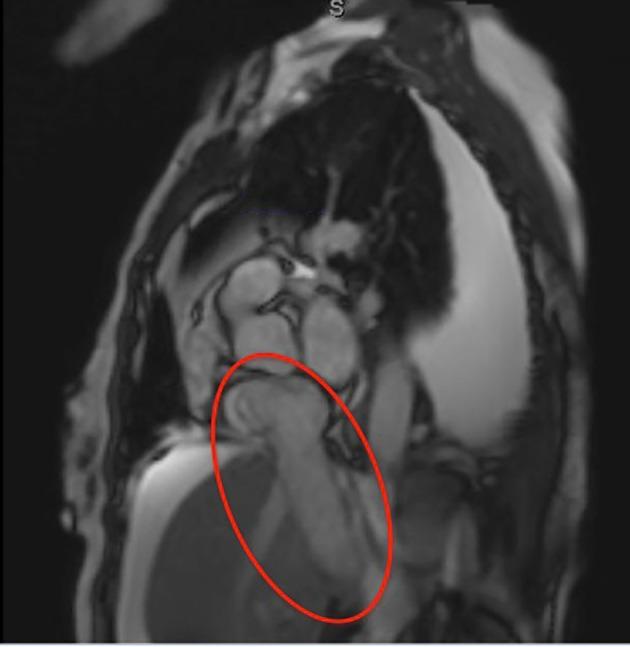

Colorectal cancers typically metastasize to the lymph nodes, liver or lungs. Metastasis to the heart is rare and although a few cases of cardiac metastases from colon cancer are described in the literature, cases of metastatic rectal cancer to the heart are far fewer. A 69-year-old woman with a history of rectal adenocarcinoma treated with neo-adjuvant chemotherapy and radiation, followed by resection and adjuvant chemotherapy, presented with increasing dyspnea on exertion and lower extremity edema 5 years after oncology follow-up. Echocardiography revealed a mass within the right atrium, which was biopsied and found to be consistent with metastatic rectal adenocarcinoma and a thrombus. The patient was deemed to be a poor surgical candidate given her co-morbidities and overall prognosis. Chemotherapy was offered and refused by the patient. The medical literature has a paucity of similar cases of rectal adenocarcinoma metastasizing to the right atrium. Further studies are needed to help guide standardized treatment options.

结直肠癌通常会转移至淋巴结、肝脏或肺部。转移至心脏较为罕见,尽管文献中描述了一些结肠癌心脏转移的病例,但直肠癌心脏转移的病例要少得多。一名69岁女性,有直肠腺癌病史,接受了新辅助化疗和放疗,随后进行了手术切除及辅助化疗,在肿瘤学随访5年后出现劳力性呼吸困难加重和下肢水肿。超声心动图显示右心房内有一肿块,经活检发现与转移性直肠腺癌及血栓相符。鉴于患者的合并症和总体预后,被认为不是手术的合适人选。提供了化疗方案,但患者拒绝。医学文献中关于直肠腺癌转移至右心房的类似病例较少。需要进一步研究以帮助指导标准化的治疗方案。